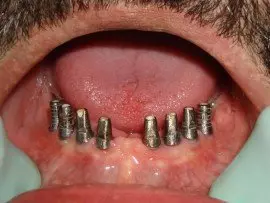

These 3 dimentional raw images run in a deisigning software and a surgical templates prepared with the anticipatory ideal dental implant positions with a cad cam technology. Specialized computer software enables implant surgeons to assess all of the critical areas of the maxillary and mandibular bone structures. The precision imaging helps dentists to not only determine the best possible implant sites but also permit the assessment of need for bone augmentation (grafting) that will optimize predictability ratios.

Computer Guided Implants : The use of surgical templates for dental implant treatment planning and placement represents one of the most innovative  development in implantology.

In order to better control the late discovery of inadequate bone structures, 3 dimentional & cross sectional images are required. Furthermore, They are now the standard level of care.